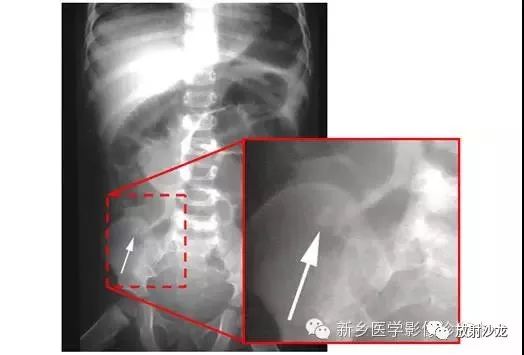

腹痛患者的腹部X光片水平位(左侧)和直立位(右侧)所上图示。是什么原因导致该病人的不适呢?

X线片表现出充满整个腹部的乙状结肠扭转。乙状结肠的两端可以理解成一个倒置的朝向骨盆的U型(图U)。在X光片直立位,可以看出气液平面(箭头)。咖啡豆的标志是乙状结肠扭转的典型的表现。充满气体的肠道包绕重叠水肿的肠壁所形成致密的白线,类似于一个咖啡豆。在这些X光片中,大肠的其余部分均不膨大,大概是因为扭转的点不造成阻塞,从而使消化产物可进入乙状结肠。